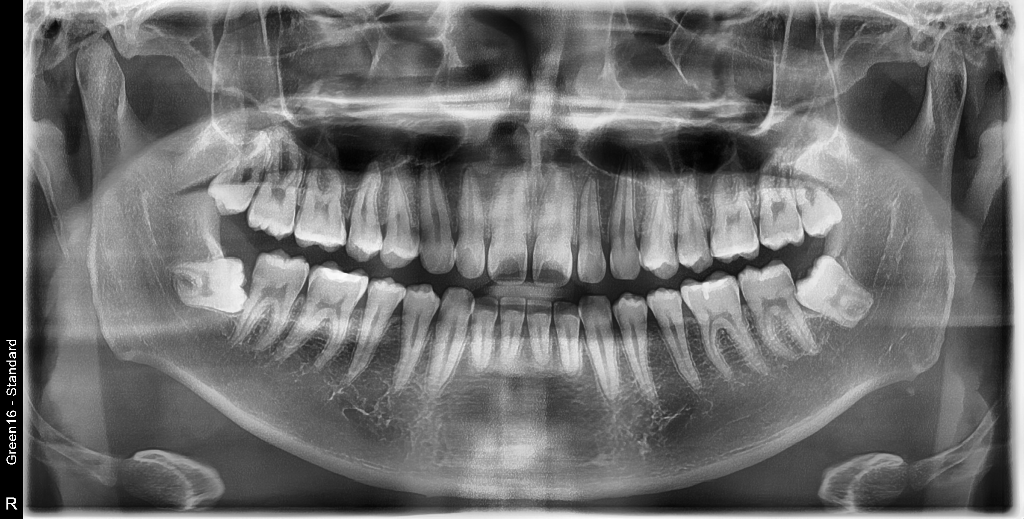

상기된 사진과 같은 치아상태에서 의사선생님이 국소적 법랑질우식이있으나 지켜보자했습니다. 헌데 요즘 게을러져서 한달 반정도를 4일에한번주기로 꼼꼼하게양치하고 치실질하는 식으로 했었는데요, 이것이 충치를 한달 반동안에 신경치료해야할만큼 위험하게 번질수도있나요?

21세 남성이고 3년간 안닦았다가 법랑질에 우식생긴이력이 있는지라 좀 우려스럽습니다

사진에서 보기에는 범랑질 표면에 살짝 표면충치가 생긴 것으로 보입니다. 범랑질 표면에 생긴 충치가 한달반 만에 상아질로 까지 진행될 가능성은 희박합니다.

충치가 교합면에도 잇고 치아 사이에도 충치가 잇는거 같습니다. 치료를 받으셔야될것같습니다.